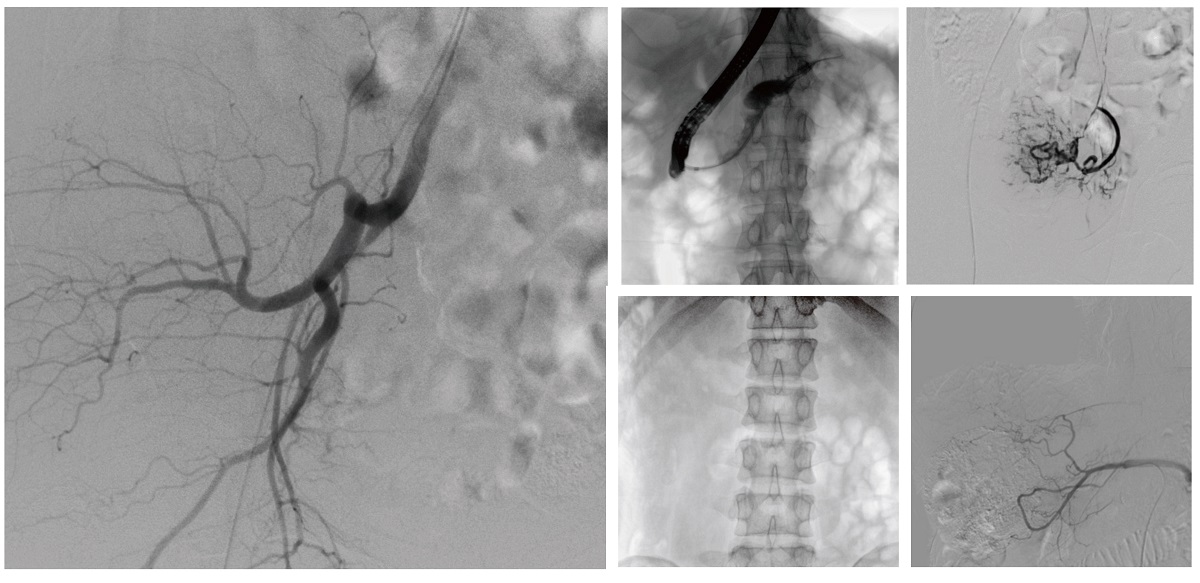

移動(dòng)式介入中C:靈活部署的“多面手”

醫(yī)院引進(jìn)的普愛醫(yī)療移動(dòng)式平板介入中C,其高清成像能力覆蓋骨科、介入科、泌尿外科、婦產(chǎn)科等多科室,能夠滿足介入微創(chuàng)手術(shù)的多樣化需求。

設(shè)備的移動(dòng)式設(shè)計(jì),無需對(duì)現(xiàn)有手術(shù)室進(jìn)行改造,適合高負(fù)荷手術(shù)量或應(yīng)急情況下的靈活部署。如在急診介入手術(shù)中,該設(shè)備能迅速響應(yīng)需求,為醫(yī)生提供實(shí)時(shí)影像支持,提升搶救效率。